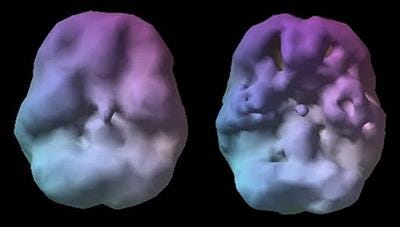

There are some very good reasons for this. I was very insecure2. And it’s fun to rib Navin3. It is remarkably easy to have extraordinary bias when confronted, as humans, with things that we find inherently convincing. One of the most convincing things that exists is pictures of brains. Not just any pictures of Brains, but the kinds of pictures that we get when we stick people in medical imaging scanners.

The most replicable finding in neuroimaging – captured in study after study – is the fact that putting a picture of a brain it next to any block of text makes it 40% more believable. I was going to look up the reference. But this is satire-edutainment so instead, it’s just a brain scan I found on the internet and we will call it a day. It’s easier than finding a reference.

This series of articles should be particularly believable because it’s going to have some pictures of brains (but because the above assertion is accompanied by an image of a brain the citation is in the footnotes4!) 🧠